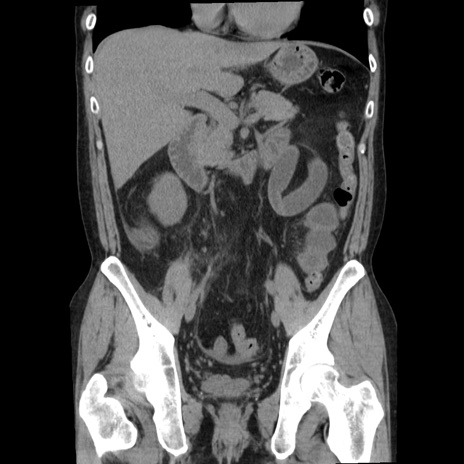

横断像

【症例】40歳代男性

【現病歴】2日前から胃痛あり。徐々に周期的な激痛に変化した。本日になっても激痛があるため受診。

【身体所見】意識清明、BT 38-39℃台あり、腹部:膨満、やや硬、右下腹部に圧痛あり。

【データ】WBC 8500、CRP 23.26